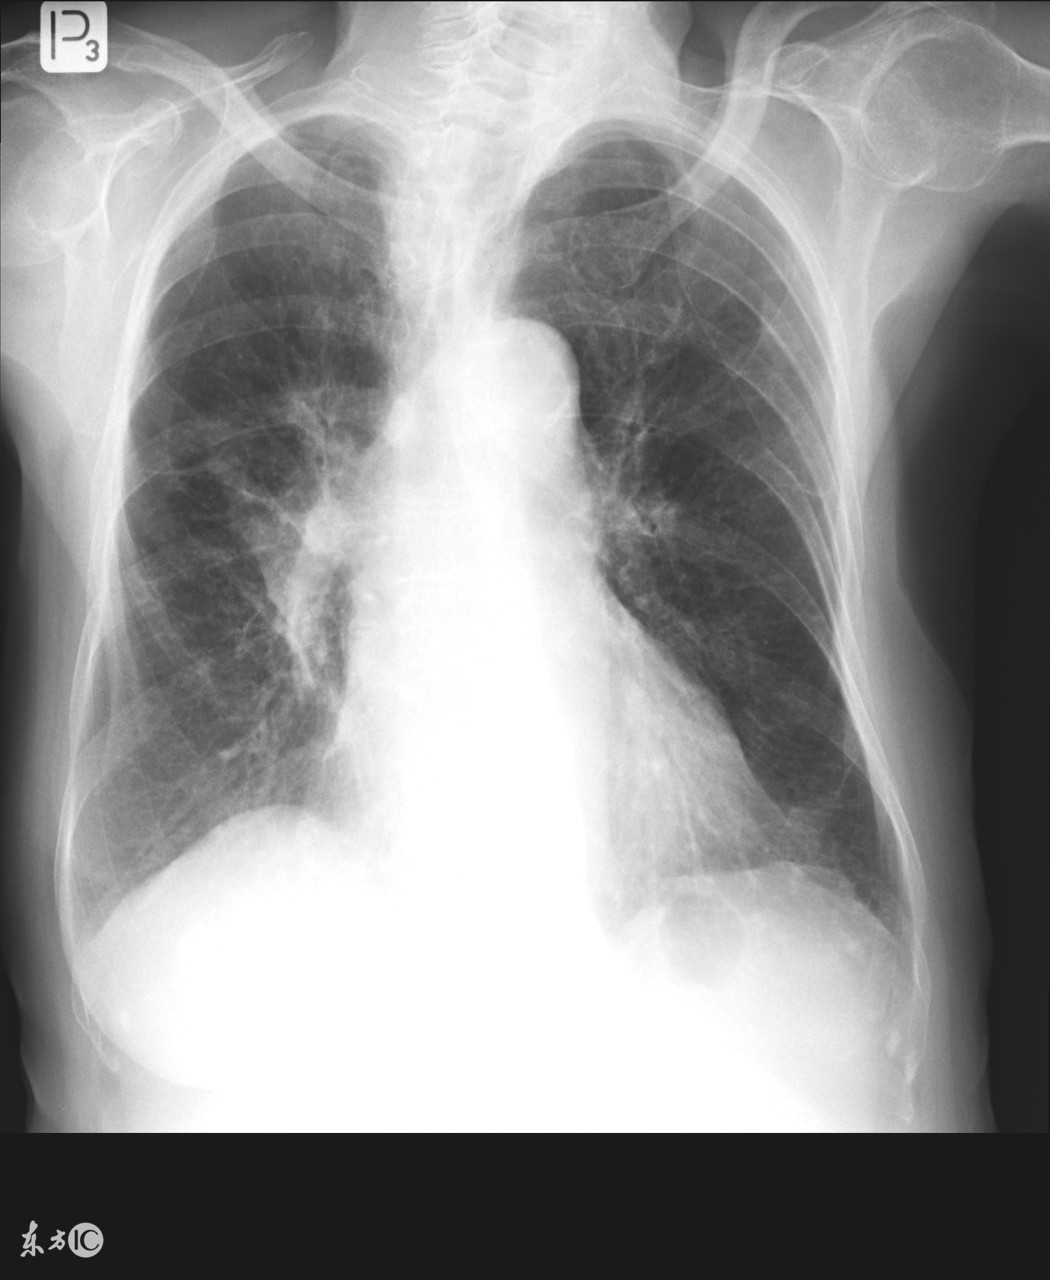

无论初治还是复治患者均要联合用药、临床上治疗失败的原因往往是单一用药造成难治病人。联合用药必须要联合二种或二种以上得药物治疗,这样可避免或延缓耐药性的产生,又能提高杀菌效果。既有细胞内杀菌药物又有细胞外杀菌药物,又有适合酸性环境内的杀菌药,从而使化疗方案取得最佳疗效。并能缩短疗程,减少不必要的经济浪费。

肺结核病人在治疗期间一定要按照医生的指示,不可以自己乱用药,也不能够自己随意停药,肺结核的治疗需要一定的周期,因此患者也需要有足够的耐心,另外在治疗期间也要注意多多运动来提高免疫力,以免造成病情恶化或者出现并发症。